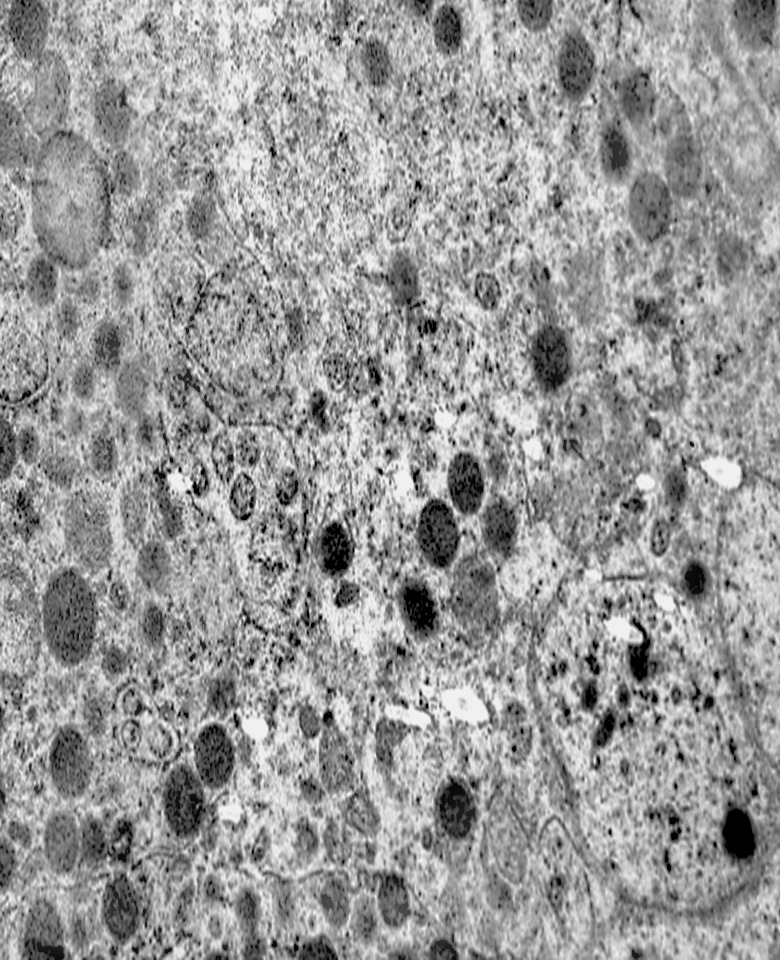

MICROAUTOFAGIA

I focolai di microautofagia si ritrovano frequentemente commisti a mitocondri disfunzionali e a reticolo- endoplasmatico in stato di stress.

Essi sono di piccole dimensioni, appaiono come vescicole, delimitate da una membrana a doppio strato, immerse nel citosol e

ricolme di materiale amorfo oppure di materiale amorfo commisto a frammenti filamentosi.

Fig.3  Fig.3a

Fig.3a